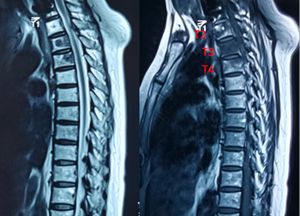

跟大家聊了很多关于脊柱转移癌的病例和科普,好像还没跟大家聊过脊柱转移癌的特点比如说什么年龄段的人好发?什么类型的癌喜欢往脊柱跑?等等。今天就跟大大家聊一聊这件事。

以前,大家听说哪个患者癌症转移了,第一个反应就是——这个人没救了。现在虽然各种各样的治疗手段都有了长足的进步,但各种癌症的转移仍然防不胜防,其中肺和肝由于血运丰富首当其冲,骨则紧随前两者之后位列第三,而脊柱则在骨转移中位列榜首!这其中原因当然是多方面的,但总归离不开原发病灶的位置。

对于脊柱转移癌而言,联合多个学科的诊断以及治疗,能够保留患者神经功能、缓解患者症状、延长患者预期生存时间,为患者带瘤生存甚至治愈争取时机。虽然每个患者年龄、肿瘤类型、预期寿命以及机体状态存在差异使得治疗方案各有不同,但一旦发现苗头积极就医才能为患者带来最大收益!